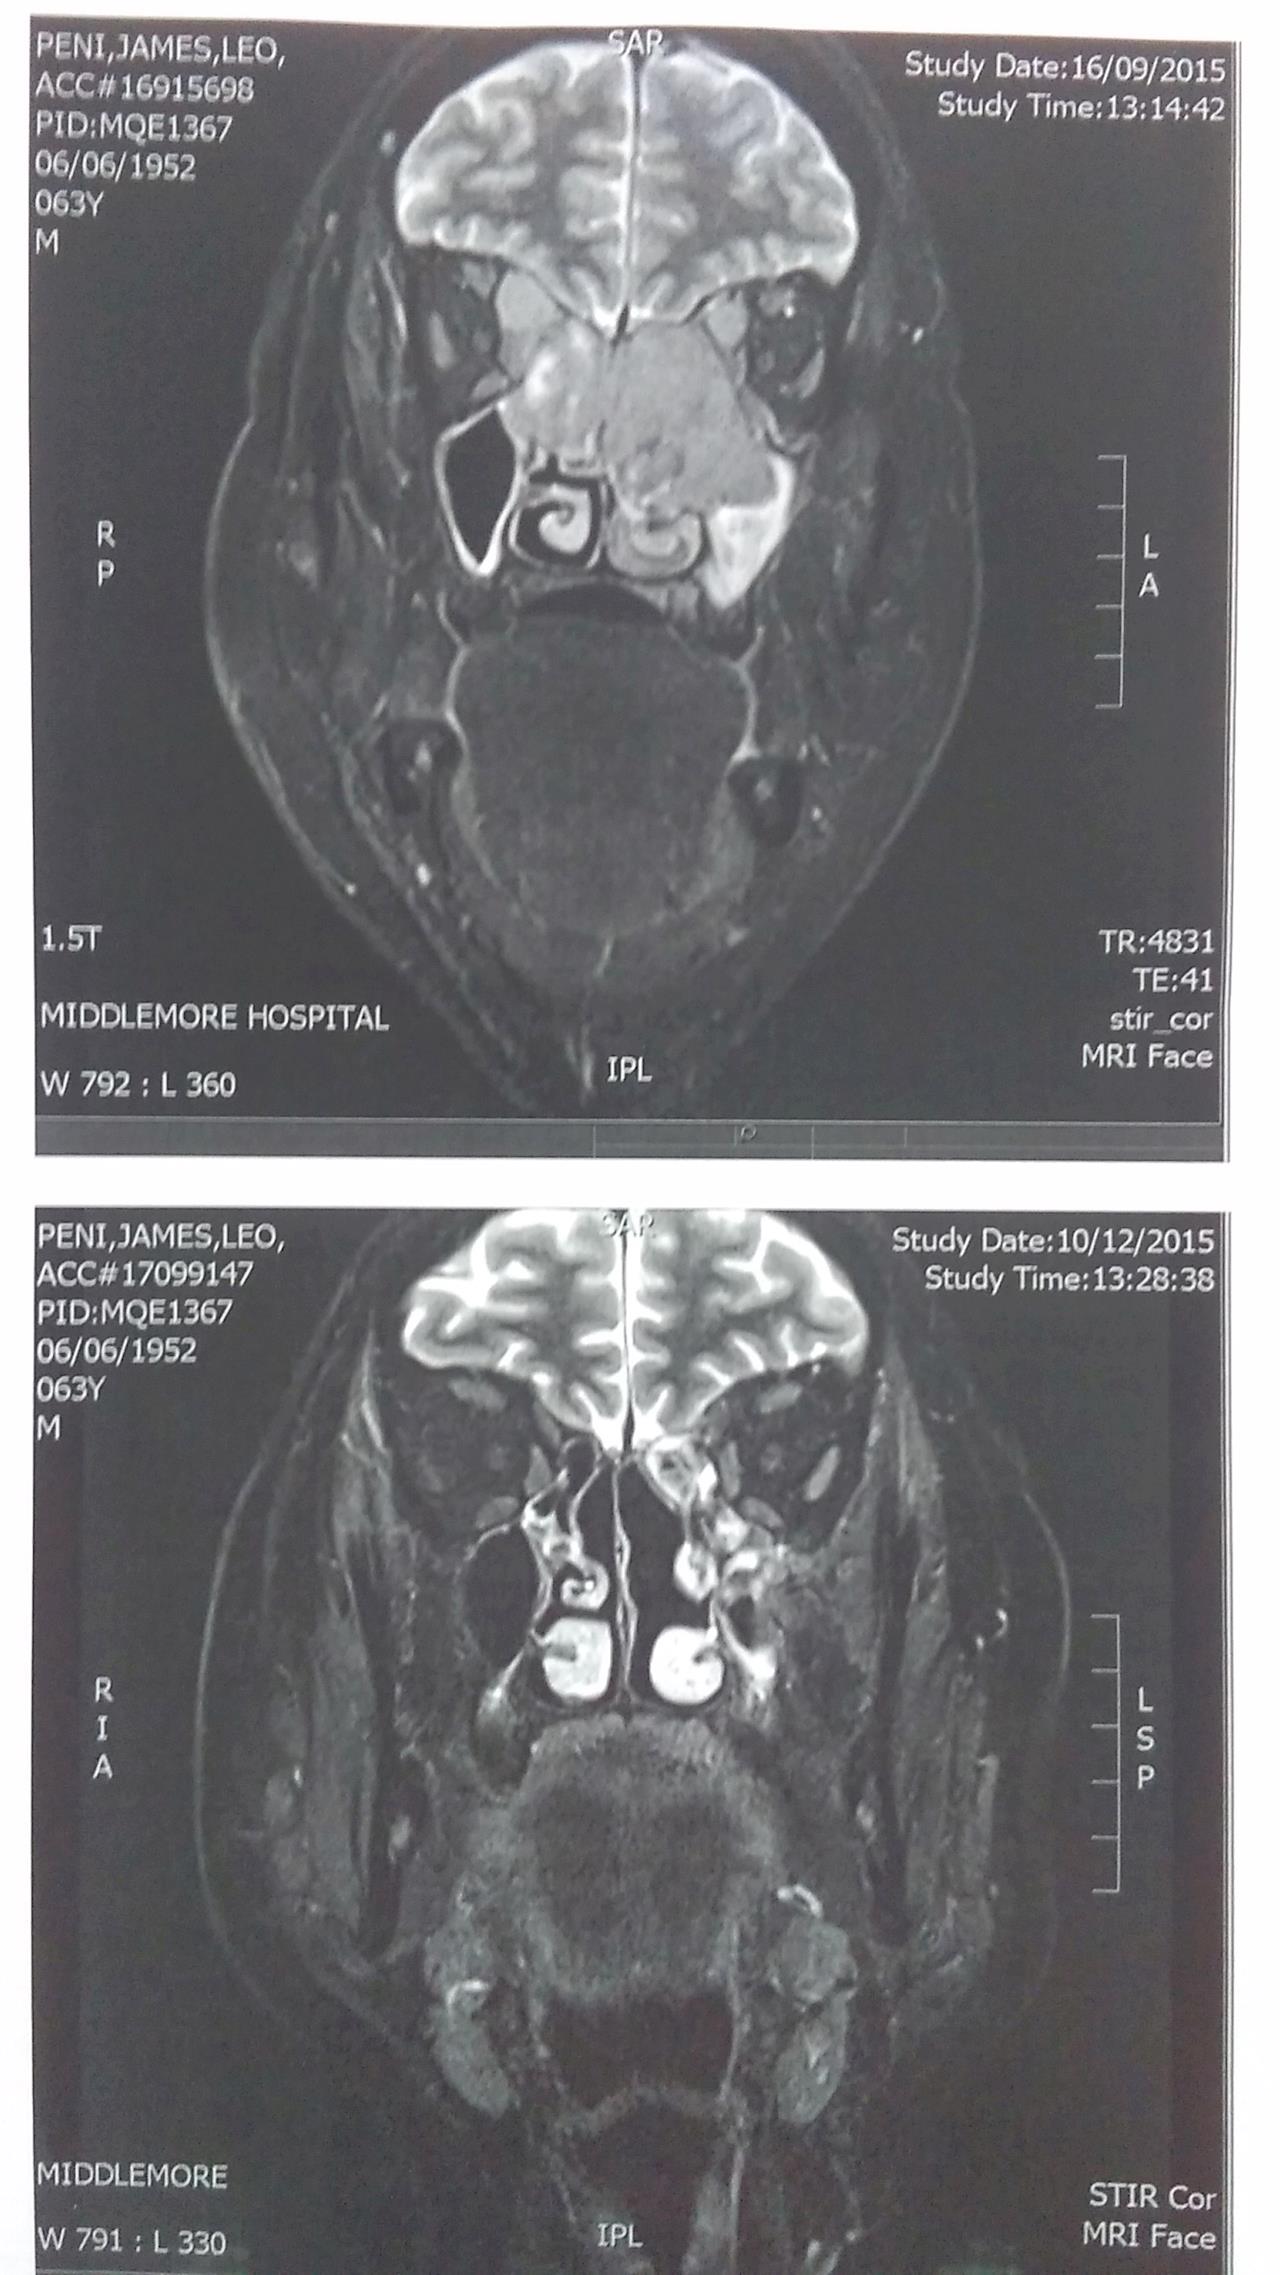

• Dads MRI scan - Pictures!

Before - top picture you can see the mass in the middle of his face ( sinus cavity)

After - bottom picture its pretty much gone

Dad calls the top one Jar Jar binks and the new bottom scan The Predator haha

Huge Huge Improvement - Positive thinking and our support does pay off